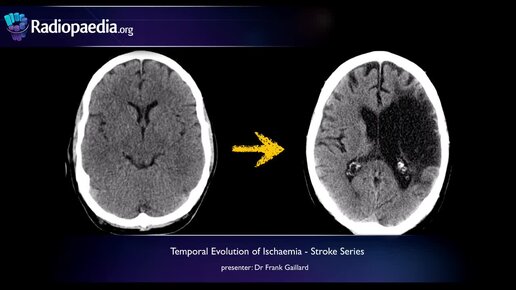

Stroke- Evolution from acute to chronic infarction - radiology video tutorial (CT, MRI)